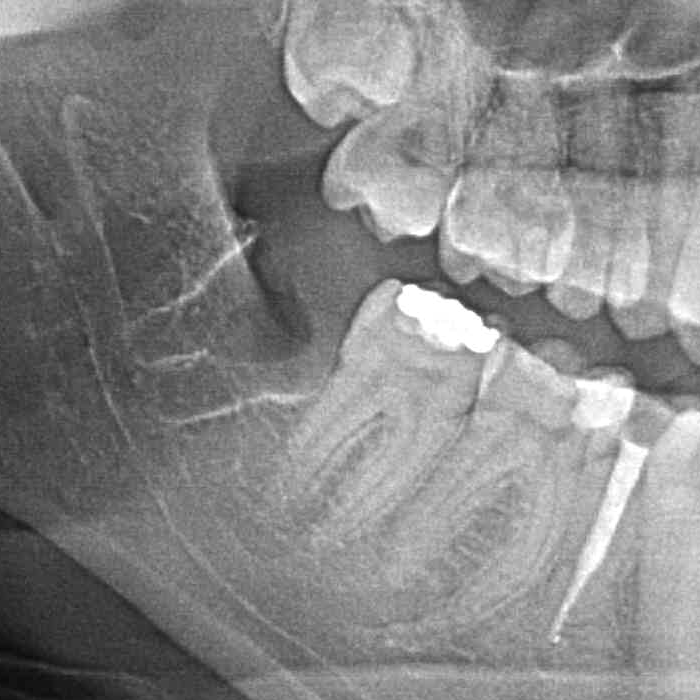

"Czy należy usuwać zęby mądrości?"- to często pojawiające się w gabinecie stomatologicznym pytanie. Każdy przypadek warto rozważyć indywidualnie, ale w większości odpowiedź brzmi: "tak". Wynika to z faktu, że ósemki często generują problemy samą swoją obecnością w jamie ustnej- niekoniecznie dlatego, że są popsute. U wielu osób zdarza się, że po prostu brakuje przestrzeni w szczęce lub żuchwie, dla prawidłowego wyżynania się i pozycjonowania tych zębów. W tym wypadku ósemki górne wrastają w policzki, a dolne blokują się pomiędzy kątem żuchwy a siódemkami dolnymi. Powoduje to po pierwsze, że zęby te generują znaczne siły działające na zęby sąsiednie często prowadząc do zniszczenia ich korzeni. Ponieważ dzieje się to w kości czasem trudno pacjentowi w porę wyczuć ten problem i dochodzi do utraty bardzo istotnych zębów nr 7. Po drugie może utrudniać higienizację ósemek, ale i siódemek co prowadzi do szybko rozwijającej się próchnicy. Po trzecie może prowadzić do stłoczenia zębów lub wykrzywiania ich w całym łuku zębowym. Kolejnym problemem może być często pojawiający się bolesny stan zapalny dziąsła- ponad rosnącą ósemką tworzy się kaptur z błony śluzowej, który zostaje zainfekowany przez zalegające bakterie z resztek pokarmowych. Nieprawidłowa pozycja ósemek sprzyja także przygryzaniu policzków co może prowadzić do powstawania w miejscach urażanych tzw. leukoplakii. Jest to schorzenie objawiające się białym rogowaceniem nabłonka jamy ustnej, a znaczny odsetek tych zmian przekształca się w nowotwór. Kolejnym przykładem na problem generowany pozostawionymi zębami mądrości są tzw. torbiele zawiązkowe powstające na bazie zawiązków tych zębów. Torbiele te nie wykryte w porę, poprzez rozrost, prowadzą do znacznych ubytków kości co grozi złamaniami np żuchwy.

PRZYKŁAD 1